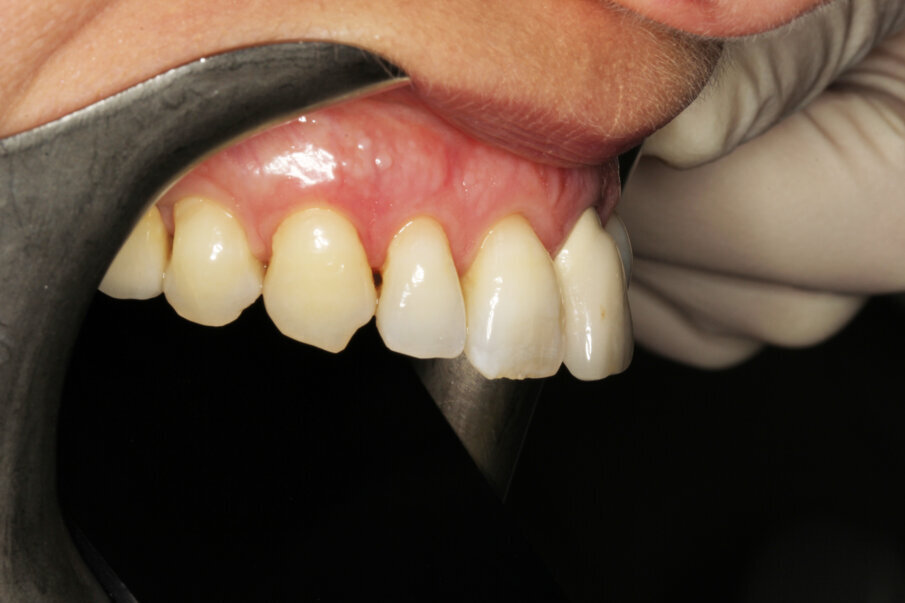

The surgeon indicated that the healing abutment may be removed after four weeks. By then, the temporary screw-retained crown had already been fabricated by the technician, who had prepared a CAD/CAM-milled acrylic tooth glued on to a Neoss NeoLink abutment (Figs. 27–30). As a result of the decision to place the implant entirely in native bone, the angulation was such as to locate the screw access hole of the provisional on the buccal aspect. This can be easily camouflaged by a simple composite filling after plugging the channel with PTFE tape. The gingival profile copies in this first stage of loading the central incisor anatomy of the Neoss Esthetic Healing Abutment (Fig. 31).

Tissue conditioning

As evidenced by the aesthetic analysis before treatment, it was clear that symmetry with the contralateral incisor would be impossible. The implant was placed slightly distal because the distal papilla normally has a narrower mesiodistal basis than the central papilla. The tissue volume augmentation helped to obtain the necessary quantity of gingiva to shape nice papillae, leaving a minimal gap. The soft tissue architecture was conditioned (Fig. 32) by adding composite to the temporary crown and grinding material where necessary until the prosthodontist and the patient felt an optimal result had been achieved.